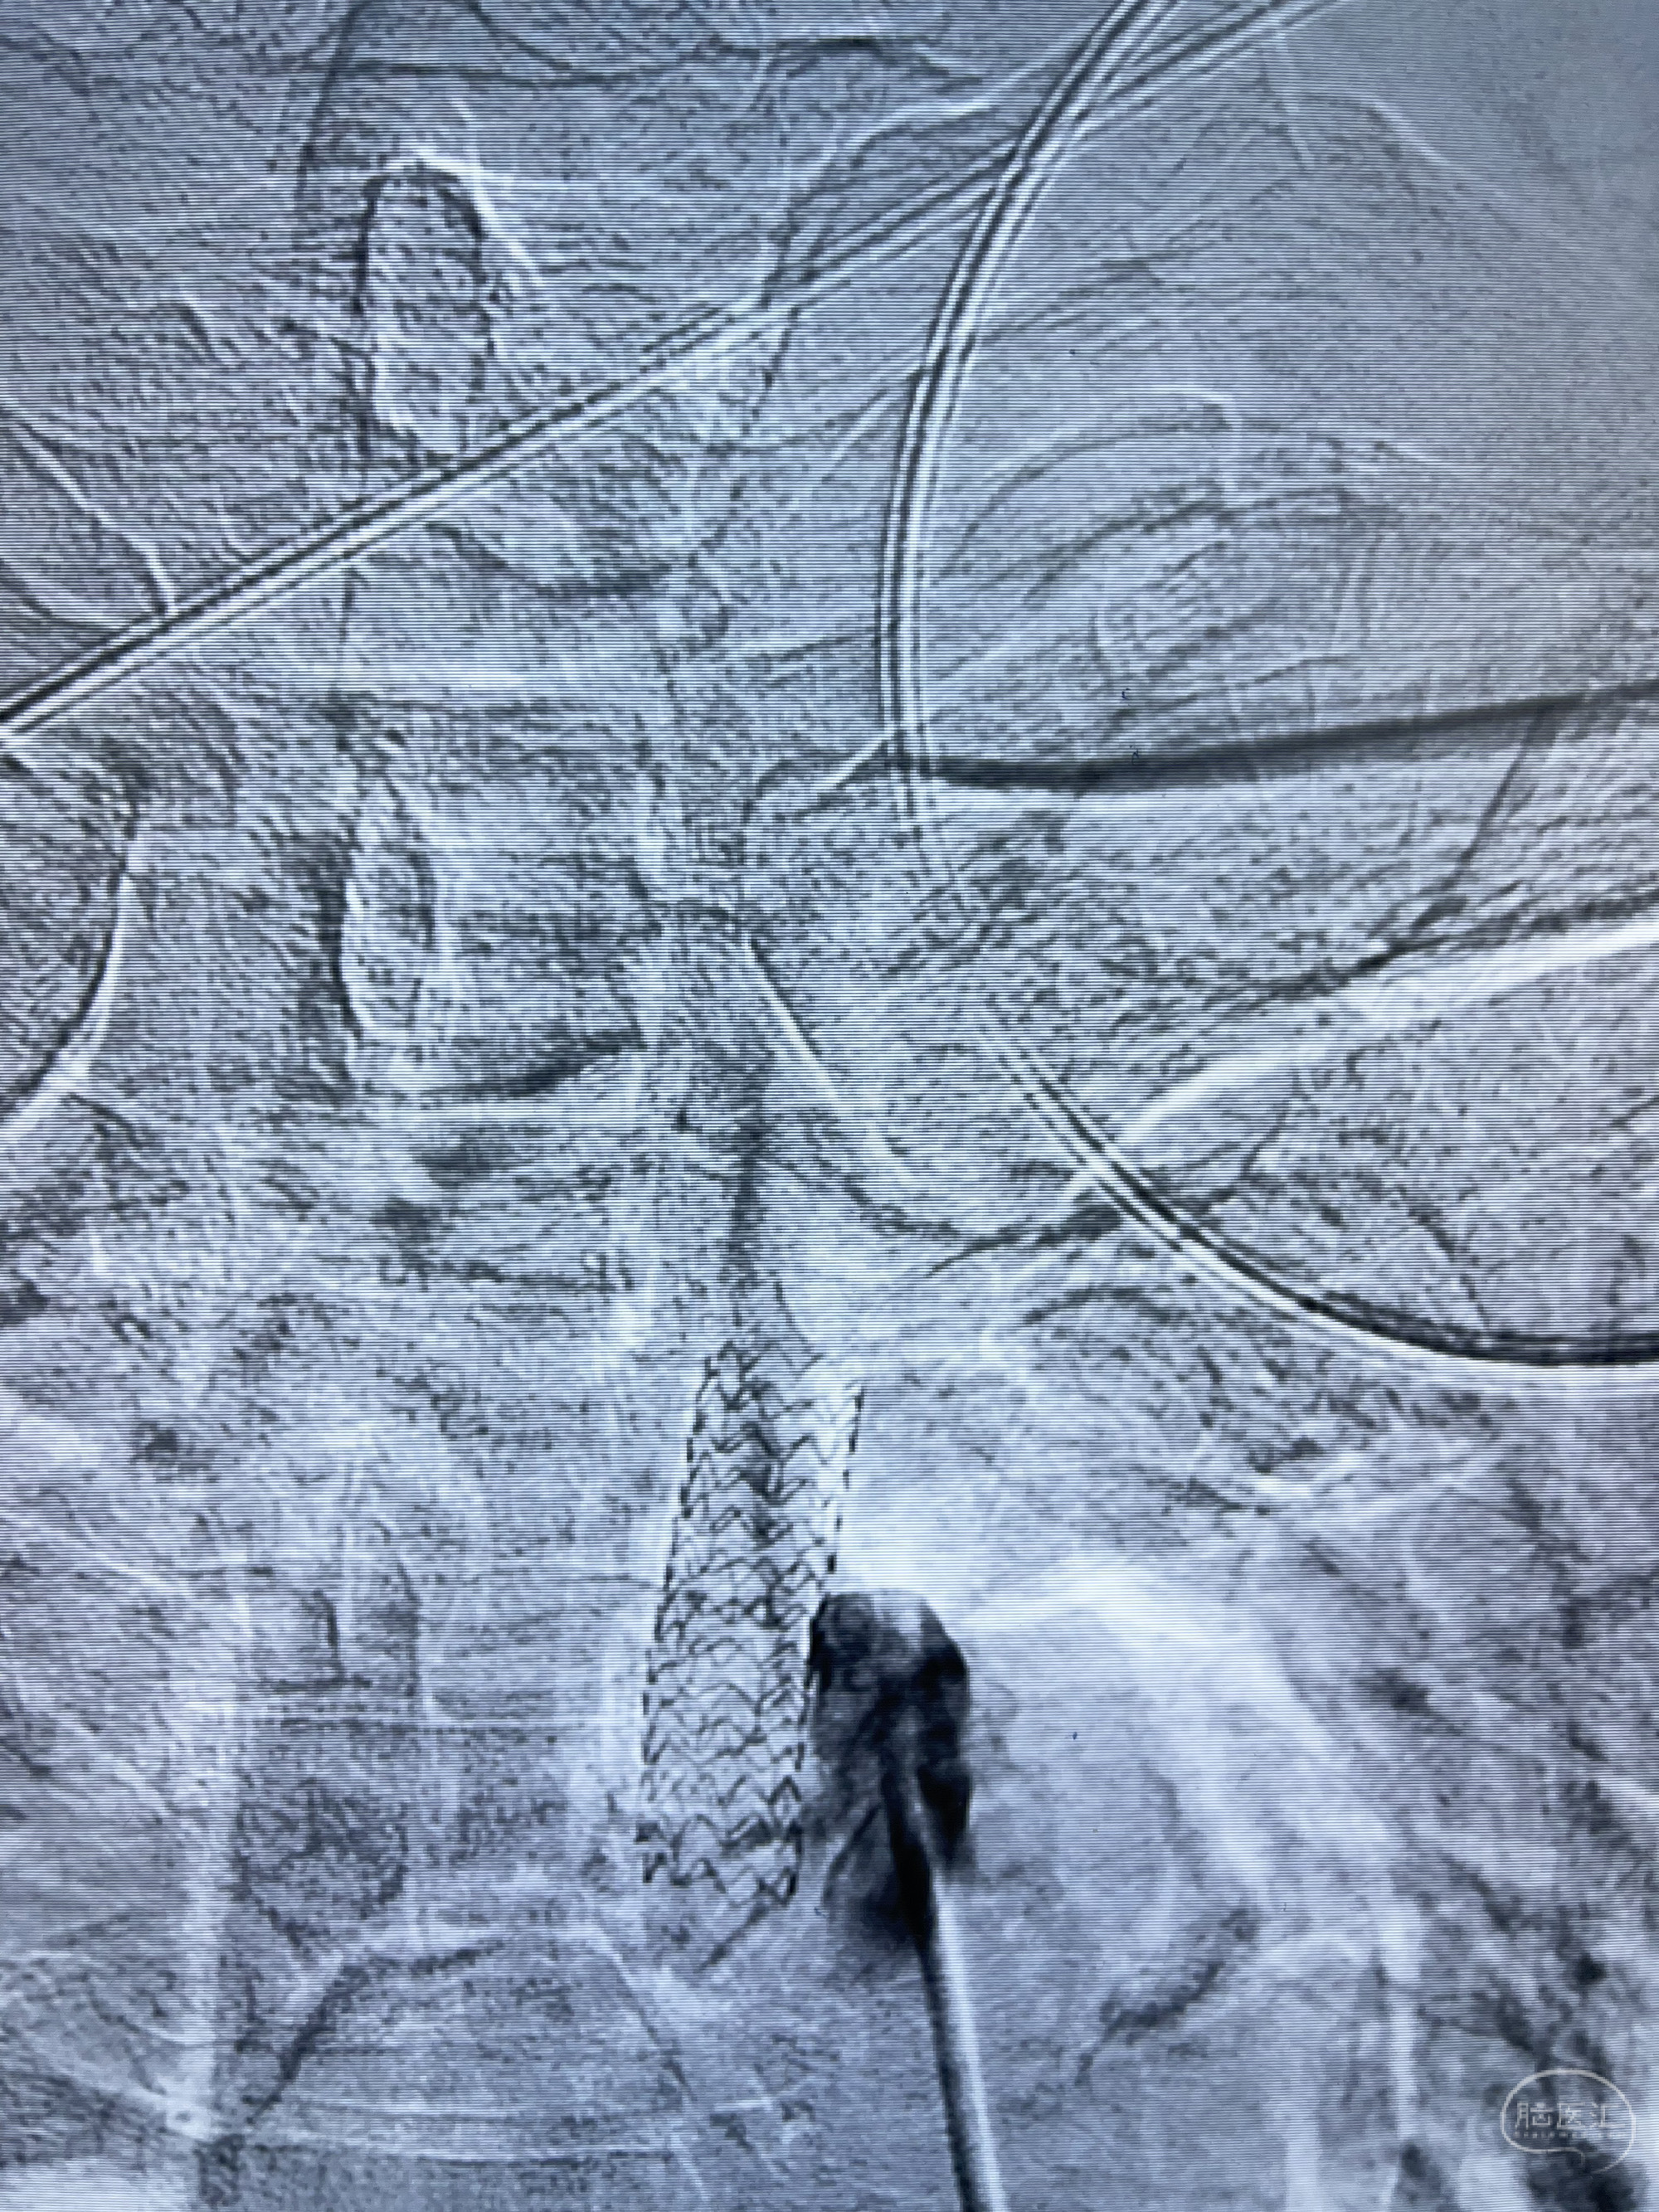

治疗策略:

1.开通左侧锁骨下动脉闭塞段

2.右侧后交通段狭窄球囊扩张➕支架辅助栓塞前壁动脉瘤?

3.左侧肾动脉狭窄球囊支架成形术